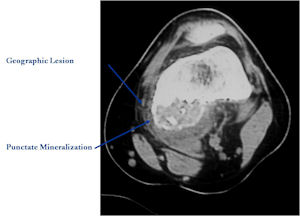

CT Scan:

- More useful for detecting mineralization and evaluating extent of bone destruction than plain X-ray

- The lesion may be entirely radiolucent but usually shows some degree of mineralization. Mineralization may appear stippled like cartilage but do not see chondroid pathologically. Mineralization is sometimes better detected on a CT scan rather than an x-ray.

- Geographic, circumscribed lesion usually around 5cm in size.

- There may be expansion of bone, cortical thinning and cortical breakthrough. A soft tissue mass may accompany this lesion but the soft tissue component is usually contained by the periosteum.

- The periosteum remains intact around the soft tissue component. Might need a CT scan to detect the subtle calcification (Egg Shell Rim of Calcification) associated with an intact periosteal reaction